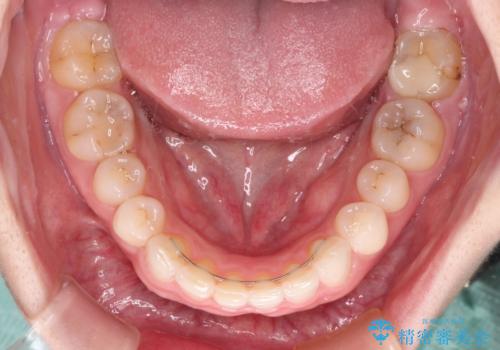

治療前、下顎前歯はほとんど見えない咬み合わせでしたが、矯正治療によりディープバイトが改善されました。

矯正治療中に前歯2本のクラウンは外れてしまい、途中仮歯に替える必要があったので期間は掛かりましたが、歯列も整い、負担のかからない咬み合わせを達成することができました。